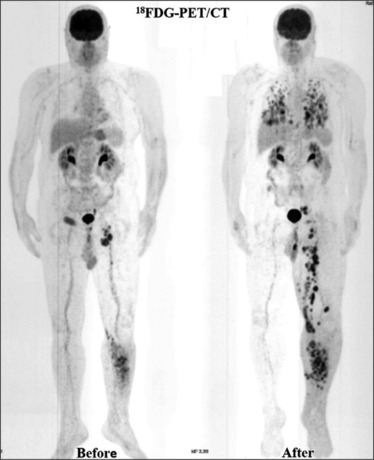

一位55岁男性晚期恶性黑色素瘤患者接受了手术、放疗和化疗。尽管进行了这些治疗,[18F]FDG PET/CT显示疾病进展明显。使用镓-68示踪剂对CXCR4、SSTR2和FAP进行靶向成像,确定了个性化治疗的生物标志物。这导致了[177Lu]Lu-FAPI-2286的选择。在第一个周期后,患者报告疼痛缓解,但随后的影像学显示快速脑转移。这个病例强调了个性化医疗和分子成像在治疗晚期黑色素瘤中的重要性。

A 55-year-old male with advanced malignant melanoma received surgery, radiotherapy, and chemotherapy. Despite these treatments, [18F]FDG PET/CT showed significant disease progression. Targeted imaging with gallium-68 radiotracers for CXCR4, SSTR2, and FAP identified biomarkers for personalized therapy. This led to the choice of [177Lu]Lu-FAPI-2286. After the first cycle, the patient reported pain relief, but subsequent imaging revealed rapid brain metastasis. This case highlights the importance of personalized medicine and molecular imaging in treating advanced melanoma.